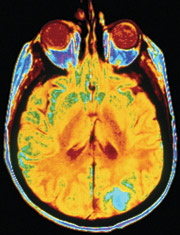

The technology, a Siemens Magnetom Allegra 3 Tesla scanner, uses a noninvasive process called functional magnetic resonance imaging (fMRI), which allows scientists to visually identify structural and functional characteristics of the human brain. Mason research faculty will now be able to see and measure how the brain functions when it is performing a variety of tasks, such as answering a question or making a decision, providing valuable information for understanding the causes of and finding new treatments and interventions for many neurological diseases, including stroke, epilepsy, Alzheimer’s disease, Parkinson’s disease, and psychiatric disorders such as Attention Deficit Hyperactivity Disorder.